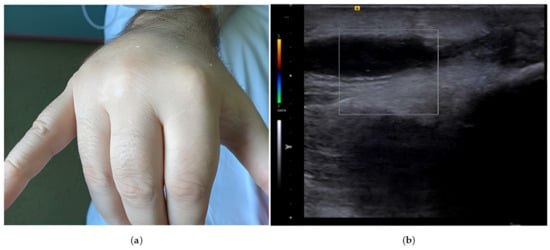

On clinical examination, the patient was febrile (39 °C), without signs of congestion, with painful mobilization of the right wrist joint, painful swelling of the dorsal region of the right hand, and of the right metacarpophalangeal joints, and flexion deformities of fingers II–IV and extension of the fifth finger and thumb (Figure 2). There was no clinical evidence of infection at the device pocket site.

Figure 2. (a) Swelling in the dorsal region of the right hand, with flexion deformities of fingers II–IV and extension of the fifth finger and thumb. (b) Ultrasound examination of the hand showing an anechoic area with no Doppler signal adjacent to the extensor tendons, suggestive of tenosynovitis.